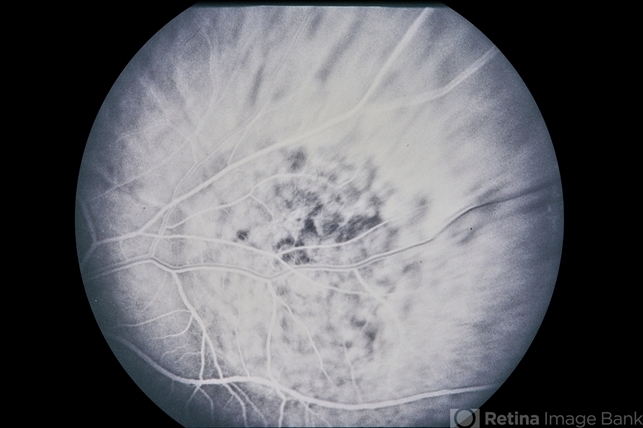

Choroidal Melanoma

68-year-old white male, choroidal melanoma.